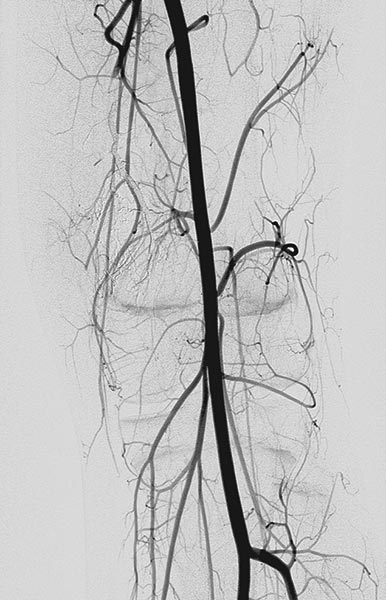

In the same session, sclerotherapy is performed using the direct puncture technique. Under ultrasound guidance, the venous malformation is punctured and contrast medium is injected.

A draining vein was immediately contrasted, which drains into the femoral vein and thus communicates with the deep conducting venous system. This communication was occluded with ethanol gel.

After occlusion of the drainage, complete sclerotherapy of the VM was possible because the liquid sclerosing agent could no longer drain off via the communicating vein.